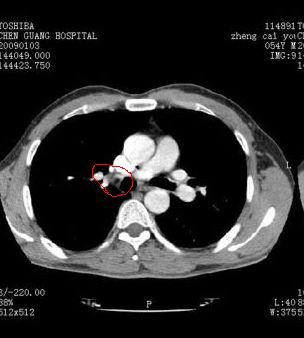

我同学讲红线部分强化不好,感觉不是很舒服,这是什么道理?

我同学讲红线部分强化不好,感觉不是很舒服,应该 是软组织间隙,不是一个孤立的病灶。